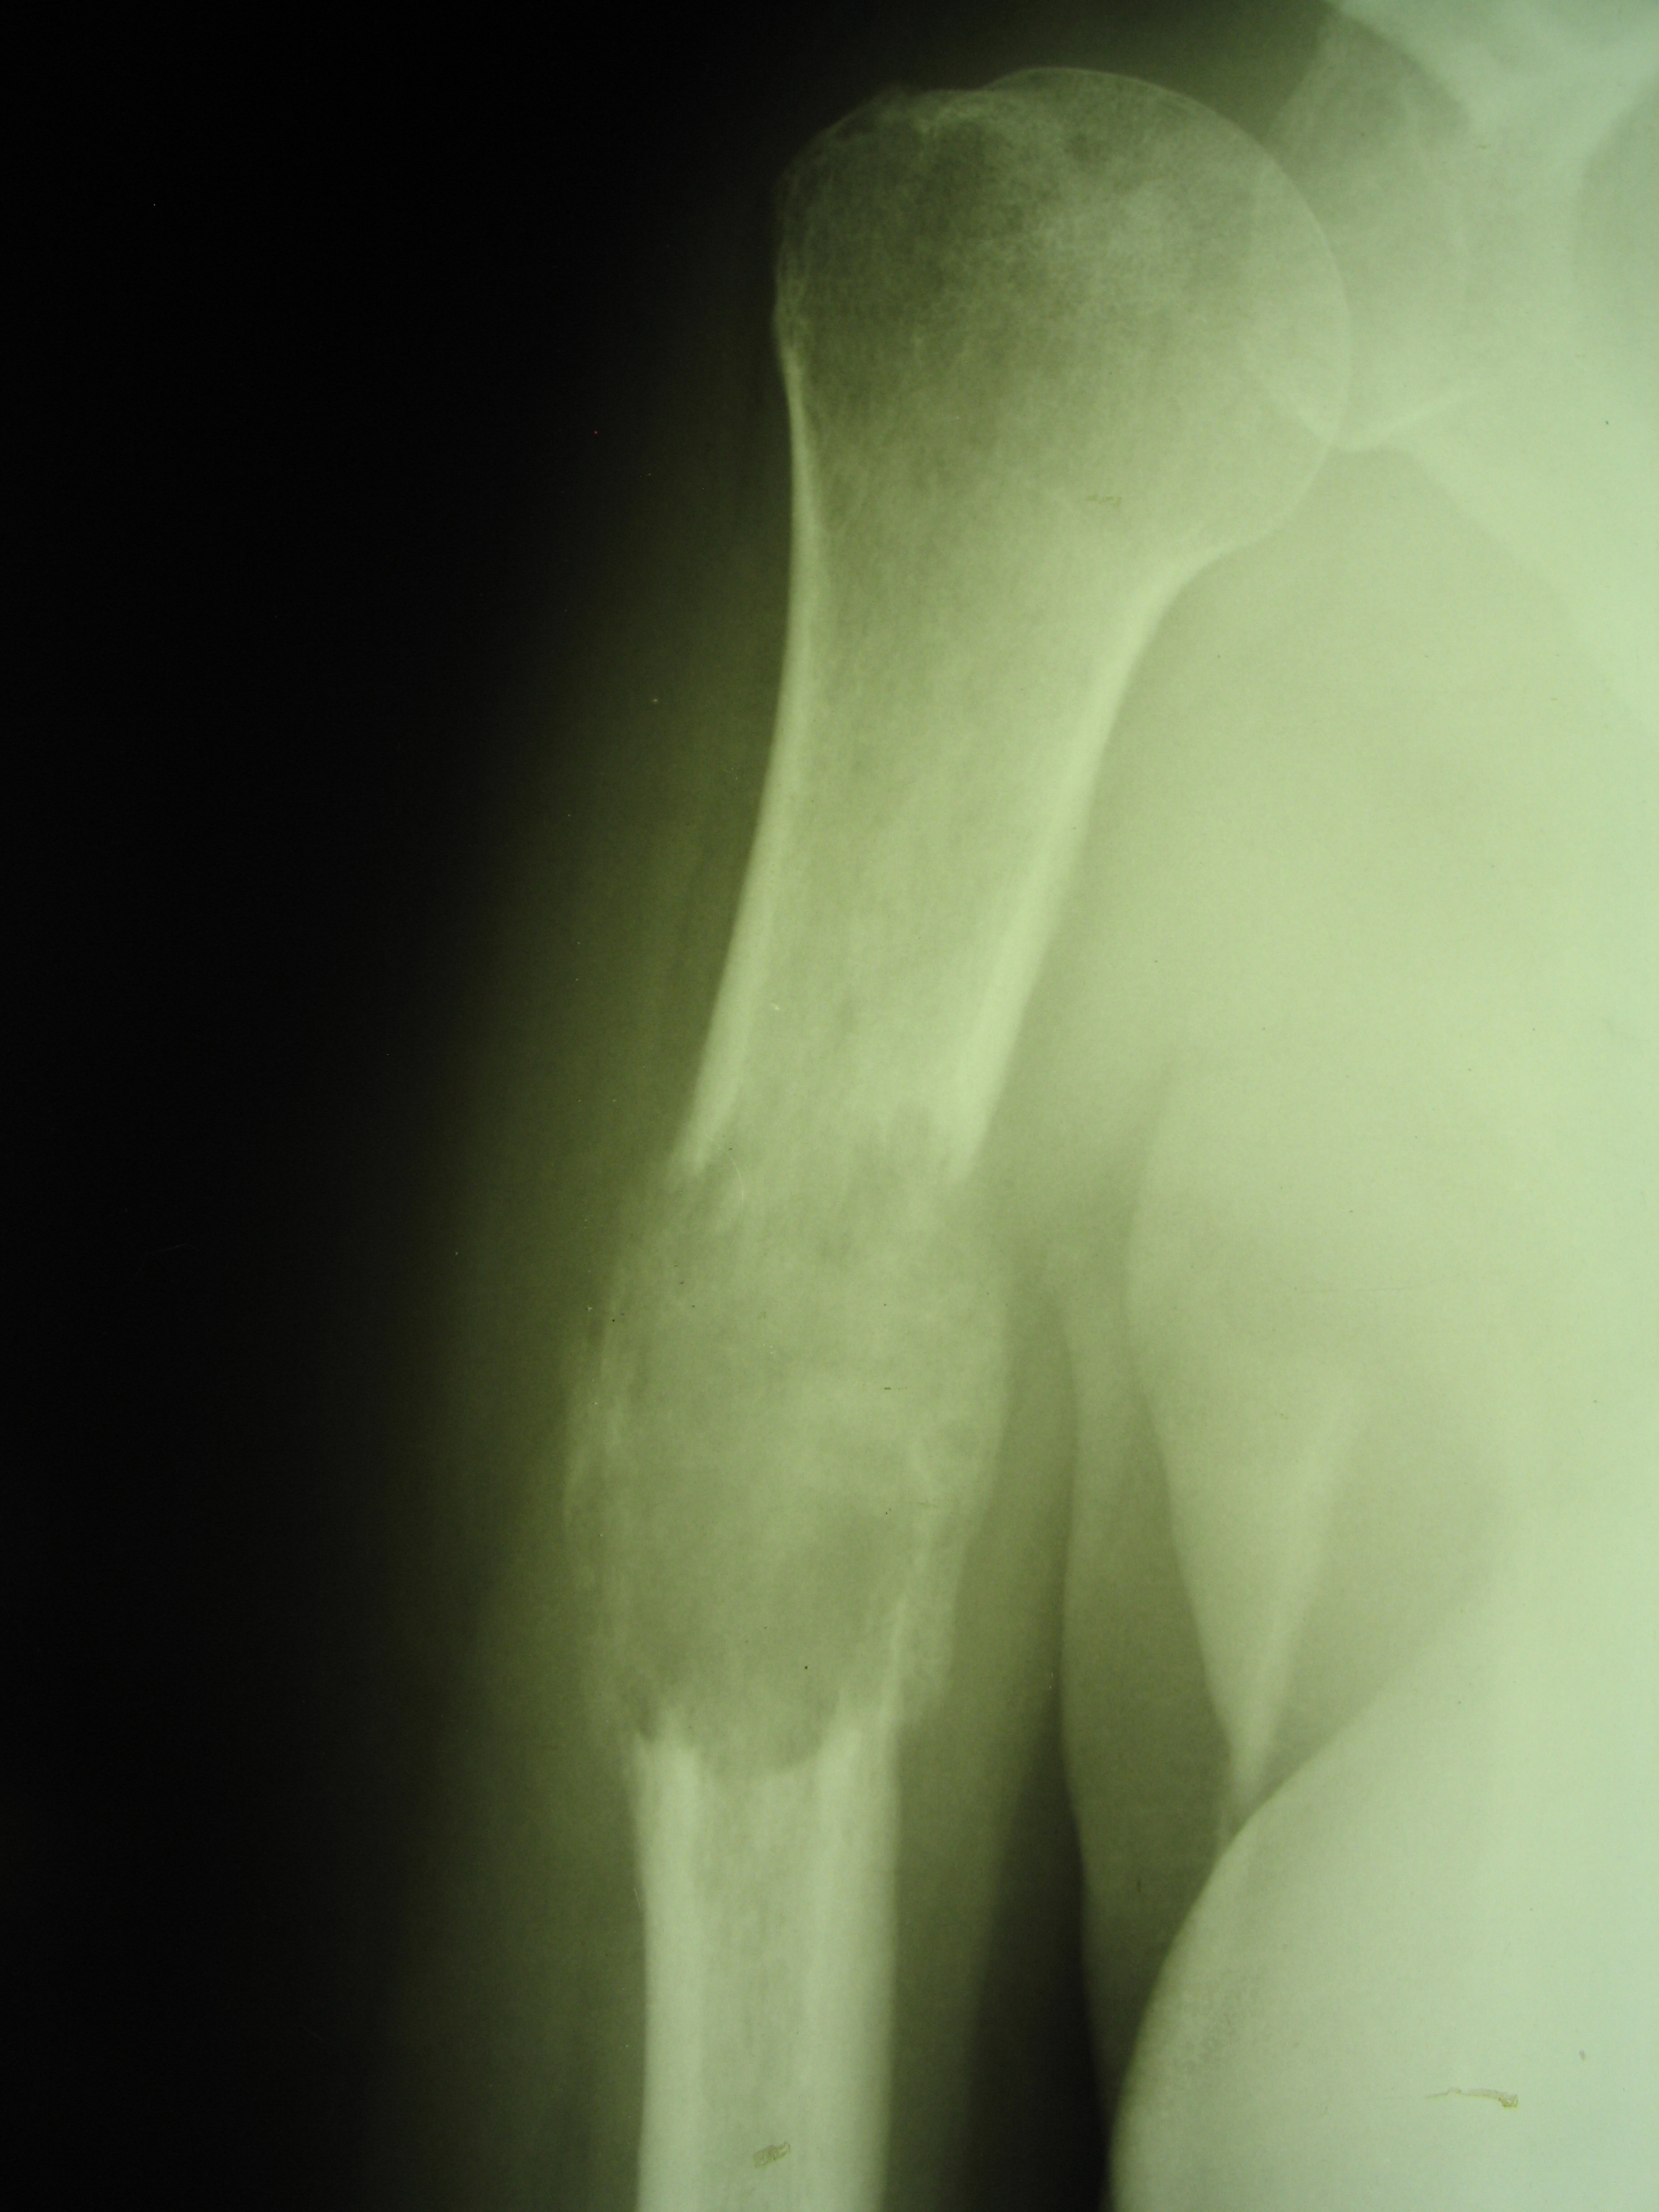

Рентгеновские снимки саркомы плечевого сустава